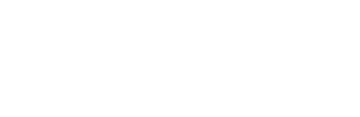

Verlicht zwangerschapsischias: ontdek natuurlijke oplossingen voor pijnvrij bewegen

Zwangerschapsischias is een veelvoorkomend probleem waarbij de groeiende baarmoeder druk uitoefent op de ischiaszenuw, wat pijn en ongemak in de onderrug, heupen en benen veroorzaakt. Natuurlijke b...